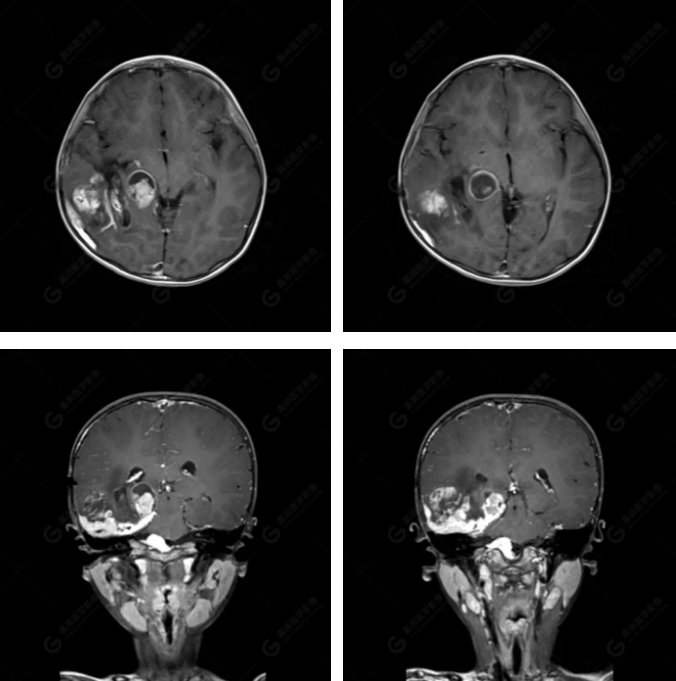

右側(cè)顳葉腫瘤切除術(shù)后(具體不詳):右側(cè)顳部骨質(zhì)不連續(xù)呈術(shù)后改變,右側(cè)顳葉術(shù)區(qū)見(jiàn)片狀長(zhǎng)T1長(zhǎng)T2信號(hào)影,F(xiàn)LAIR呈低信號(hào);術(shù)區(qū)后方右側(cè)顳枕葉見(jiàn)一巨大占位性病變影,邊界欠清,大小約6.2×5.8×4.3cm(前后×左右×上下),信號(hào)不均勻,T1WI呈等稍低信號(hào)間雜少許高信號(hào),T2WI呈高稍低混雜信號(hào),DWI示部分病灶彌散受限,相應(yīng)ADC圖減低,磁敏感序列見(jiàn)部分呈極低信號(hào),增強(qiáng)掃描可見(jiàn)明顯不均勻強(qiáng)化,鄰近硬腦膜及小腦幕增厚并明顯強(qiáng)化;另延髓右前方及右側(cè)橋小腦角區(qū)見(jiàn)一不規(guī)則形異常信號(hào)影,大小約3.2×1.3×3.7cm(左右×前后×上下),呈長(zhǎng)T1稍長(zhǎng)T2信號(hào),F(xiàn)LAIR呈等信號(hào),DWI未見(jiàn)受限,增強(qiáng)后明顯均勻強(qiáng)化,鄰近腦膜明顯強(qiáng)化。鄰近腦實(shí)質(zhì)及右側(cè)顳角明顯受壓;左側(cè)大腦半球未見(jiàn)局灶性信號(hào)異常,中線結(jié)構(gòu)稍左移。

右側(cè)顳葉腫瘤切除術(shù)后:現(xiàn)術(shù)區(qū)后方右側(cè)顳枕葉及延髓右前方占位,右側(cè)顳枕部硬腦膜及小腦幕明顯強(qiáng)化,結(jié)合既往影像資料,考慮為胚胎源性惡性腫瘤,如非典型畸胎樣/橫紋肌樣瘤(AT/RT)或原始神經(jīng)外胚層腫瘤(PNET)。

術(shù)后隨訪病理結(jié)果:非典型畸胎樣/橫紋肌樣瘤。